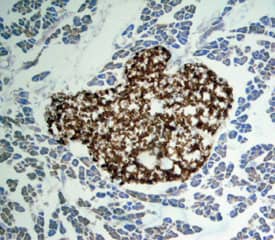

Apolipoprotein H/ApoH antibody in Mouse Pancreas by Immunohistochemistry (IHC-Fr).

Apolipoprotein H/ApoH in Mouse Pancreas.

Apolipoprotein H/ApoH was detected in perfusion fixed frozen sections of adult mouse pancreas using Goat Anti-Human Apolipoprotein H/ApoH Antigen Affinity-purified Polyclonal Antibody (Catalog # AF5087) at 15 µg/mL overnight at 4 °C. Tissue was stained using the Anti-Goat HRP-DAB Cell & Tissue Staining Kit (brown; Catalog # CTS008) and counterstained with hematoxylin (blue). Specific staining was localized to pancreatic islets. View our protocol for Chromogenic IHC Staining of Frozen Tissue Sections.